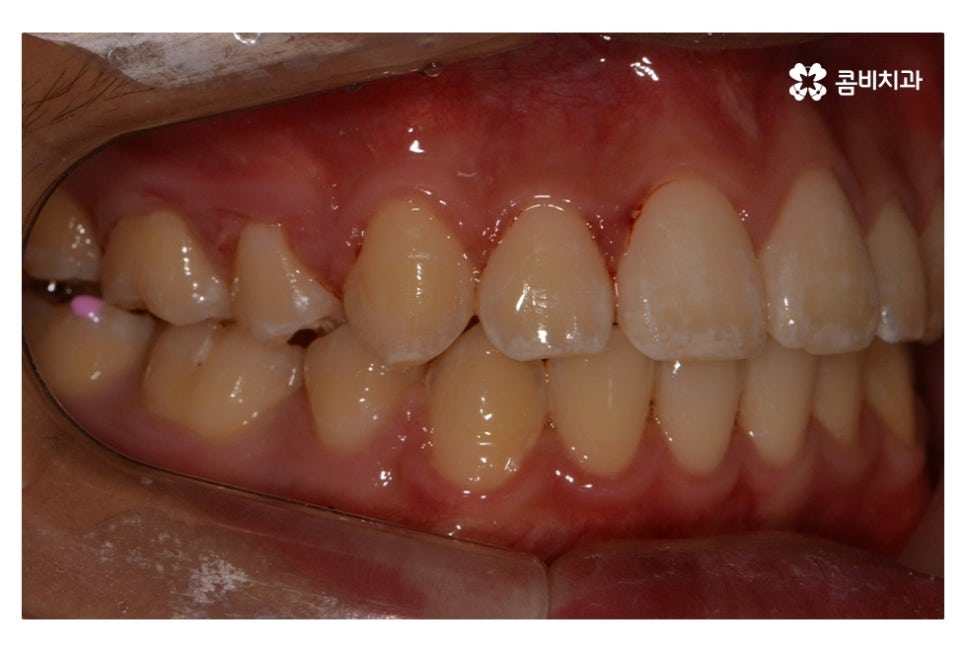

오늘 보여드릴 중학생치아교정 사례의 경우에는

악골의 위치는 정상적인 상태에서 불규칙한 치열로 인해

교정 치료를 진행한 사례라고 할 수 있어요.

위 환자분의 경우 발치가 진행된 사례로 치아의 이동 공간을

고려할 때 발치가 필요했고 환자분도 보다 나은

심미성을 위해서 동의한 상황이라고 할 수 있어요.

위 사진에서 보시면 시간이 지나면서 발치를 했던 치아의

공간이 사라지고 교정을 통해서 치열이 가지런해진 것을 확인할 수 있는데요.

중학생치아교정에 있어서 중요한 사항이 단지 치열만이

가지런해 보이는 것이 아닌 얼굴과의 조화와 교합이라 할 수 있어요.